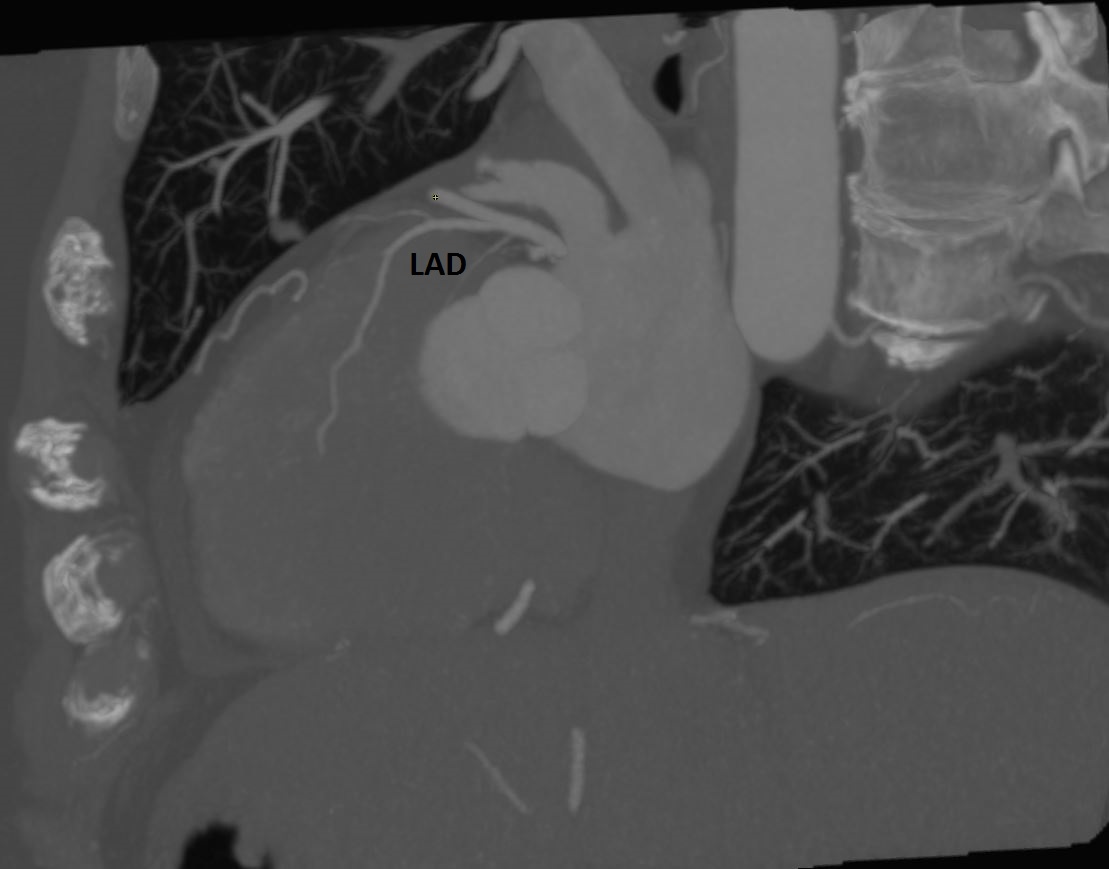

Reading #YesCCT I have seen many intramuscular LAD but this one struck me as particularly deep in the myocardium and long (44mm) in a chest pain pt #MorristownCards @Heart_SCCT @mmartinezheart @LindaGillamMD @CardiacConsult @lillian_aldaia @PhilGenereuxMD